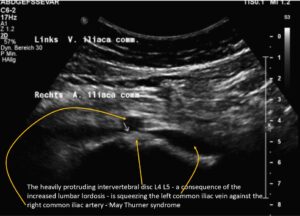

Further upstream the next outflow obstruction from the left leg is a May-Thurner syndrome due to a severe compression of the left common iliac vein:

The subsequent congestion of the pelvic circulation was massively aggravated by a left renal vein compression which pours large amounts of blood towards the pelvic circulation via its collaterals-mainly the left ovarian vein. Due to the obstruction of the pelvic outflow the additional large left renal collateral flow volume is massively affecting the outflow from the left leg thus fuelling the chronic regional pain syndrome there.

The exaggerated lumbar lordosis was compressing the inferior vena cava, which increased the backflow pressure in the left leg.